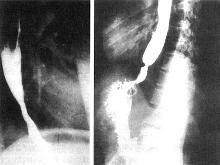

(1) X線檢查可確定腫瘤的上、下範圍,尤其是雙對比造影,對治療有一定參考價值。若要根據食管的擴展性來判斷病源範圍、食管周圍的侵蝕及淋巴結轉移和疾病分期,則必須依靠CT檢查。(2) 食管異物檢查首先應透視頸部及胸部,以觀察是否有不透X線的異物存留,然後可口服浸以鋇劑的棉花球,如棉花球停留在一個固定部位而不再下降時,應懷疑有異物存在的可能。此法對雞骨或魚骨刺有效,但有時有假陽性,應結合患者的病史及食管鏡檢查進行最後確診。(3) 氣鋇雙重對比造影,可清晰顯示食管黏膜結構。